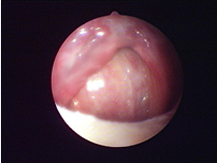

對軟組織切口的比較